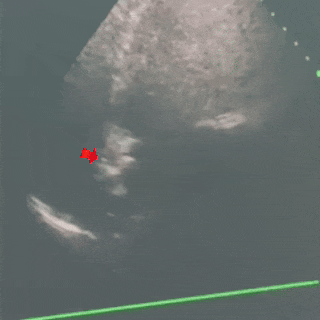

TEE超声所见:房间隔回声中断不明显,略向右心房膨出,宽度18mm,深度5mm,略有摆动,卵圆窝处较薄,未见房水平分流,左房侧开口约1.2mm,右房侧开口不明显,瓦氏动作后左房侧开口约1.5mm,右房侧开口约2.5mm,可见房水平少量左向右分流,隧道长度约12mm,继发隔厚度约3mm,右房内可见下腔静脉瓣,长度约29mm,摆动明显。

超声诊断:房间隔卵圆孔未闭,体部及耳部未见明显血栓

右心声学造影:10ml手振生理盐水,经左上肢贵要静脉快速注入,右房充分显影,静息状态第二个心动周期左心房内见中等量微泡进入,瓦氏动作后即刻左心房内见大量微泡进入。

超声提示:心房水平可见右向左分流(大量)。

超声下左盘贴壁

术后超声

超声下可见封堵器左右盘面牢牢贴靠房间隔,且无残余分流,封堵成功